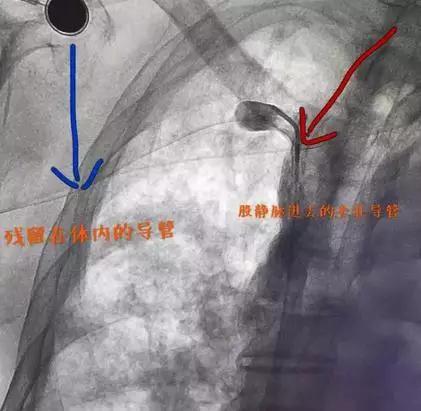

2、胸片确定断裂导管黏贴在血管内,头端仍在上腔静脉内,未发生漂移,无立即急行取除指征。和DSA科医生预约,确定取除方案。

3、四个小时后送病人去DSA室,局麻后经右侧股静脉入路,猪尾套扎导管在导丝配合下,经髂静脉-下腔静脉-右心房-上腔静脉,见到PICC残留导管给予松解套扎后,慢慢拖拽至右心房-下腔静脉-髂静脉-股静脉,最后被顺利取出。

▲ 进行套扎取除过程图像